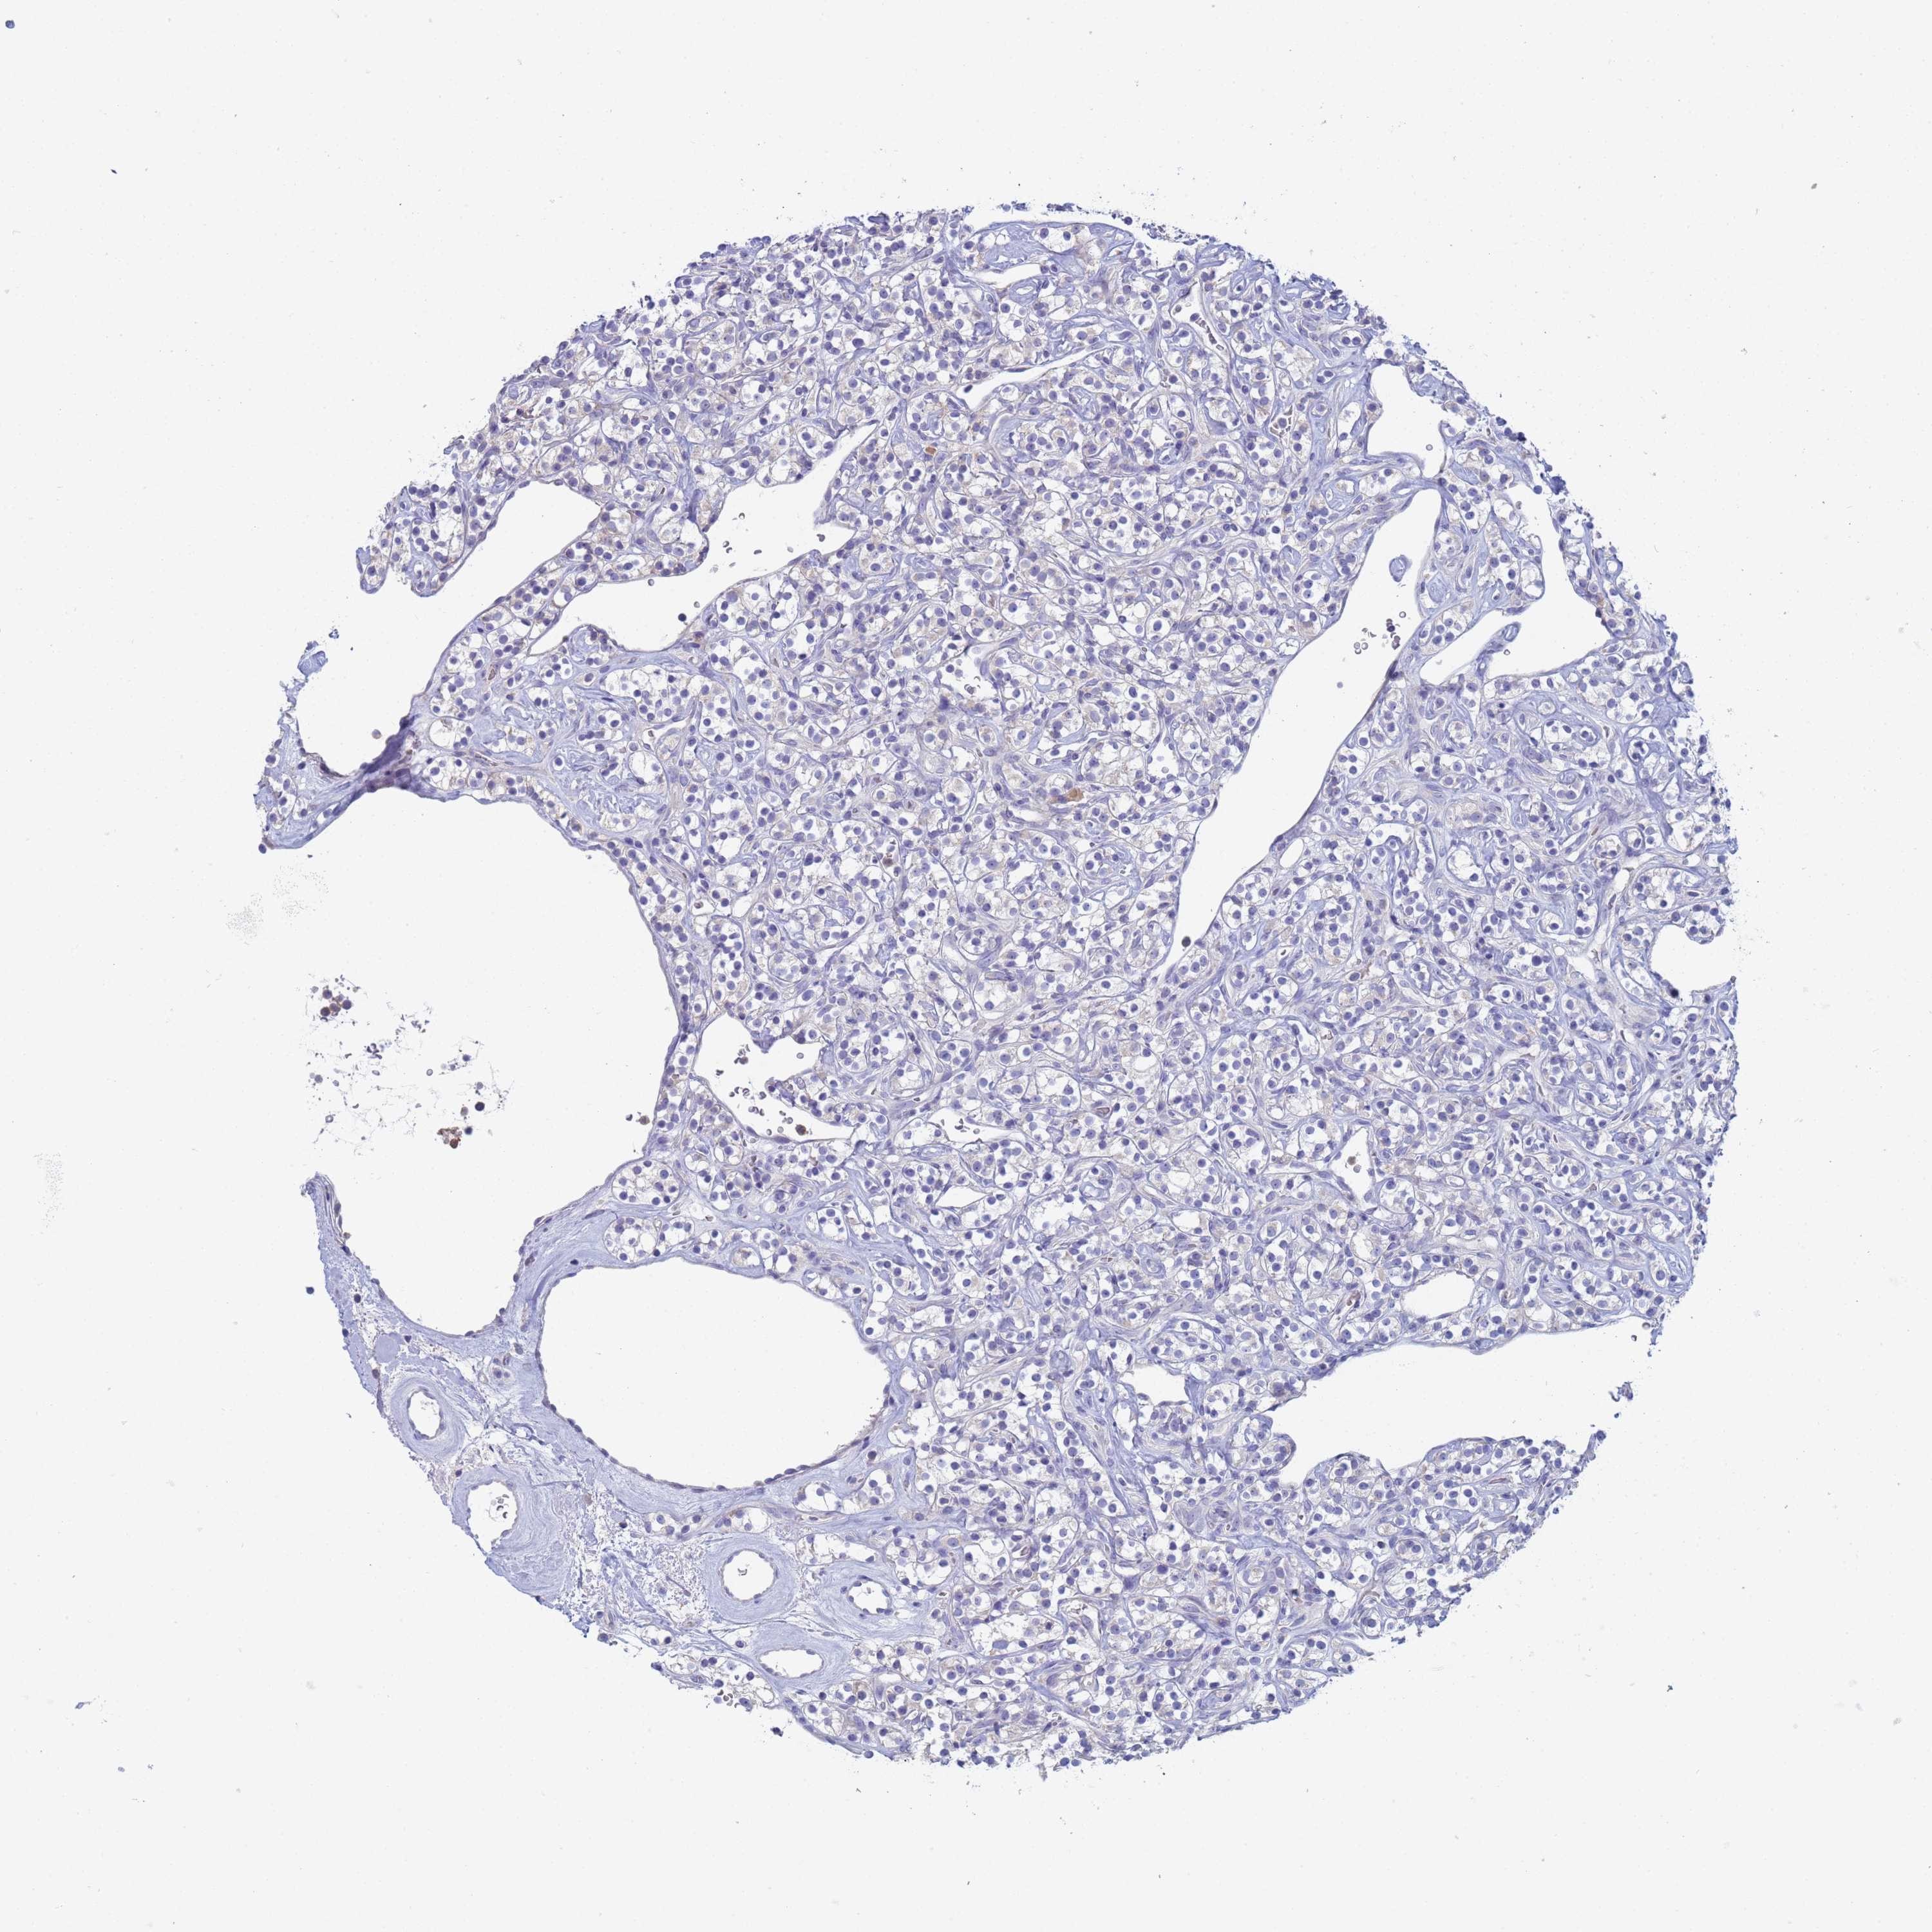

KIDNEY RENAL PAPILLARY CELL CARCINOMA (TCGA) - Interactive survival scatter ploti

The Survival Scatter plot shows the clinical status (i.e. dead or alive) for all individuals in the patient cohort, based on the same data that underlies the corresponding Kaplan-Meier plots. Patients that are alive at last time for follow-up are shown in blue and patients who have died during the study are shown in red.

The x-axis shows the expression levels (FPKM) of the investigated gene in the tumor tissue at the time of diagnosis. The y-axis shows the follow-up time after diagnosis (years). Both axes are complimented with kernel density curves demonstrating the data density over the axes. The top density plot shows the expression levels (FPKM) distribution among dead (red) and alive patients (blue). The right density plot shows the data density of the survived years of dead patients with high and low expression levels respectively, stratified using the cutoff indicated by the vertical dashed line through the Survival Scatter plot. This cutoff is automatically defined based on the FPKM cutoff that minimizes the p-score. The cutoff can be changed by dragging the vertical line or by entering a cutoff value in the square labeled "Current cut-off".

Under the Survival Scatter plot the p-score landscape (black curve; left axis) is shown together with dead median separation (red curve; right axis). Dead median separation is the difference in median mRNA expression between patients who have died with high and low expression, respectively. It is calculated as follows: median FPKM expression of dead patients with high expression - median FPKM expression of dead patients with low expression. This is intended to aid the user in visually exploring custom cutoffs and the associated p-scores and dead median separation.

Individual patient data is displayed and can be filtered by clicking on one or more of the category buttons on the top of the page. Categories describing expression level and patient information include: high, low, alive, dead, female, male and tumor stages. The scale of the x-axis can be toggled between linear and log-scale by clicking on the "x log" button. Mouse-over function shows TCGA ID, patient information and mRNA expression (FPKM) for each patient.

& Survival analysisi

Kaplan-Meier plots summarize results from analysis of correlation between mRNA expression level and patient survival. Patients were divided based on level of expression into one of the two groups "low" (under cut off) or "high" (over cut off). X-axis shows time for survival (years) and y-axis shows the probability of survival, where 1.0 corresponds to 100 percent.

CR1 is not prognostic in Kidney Renal Papillary Cell Carcinoma (TCGA)